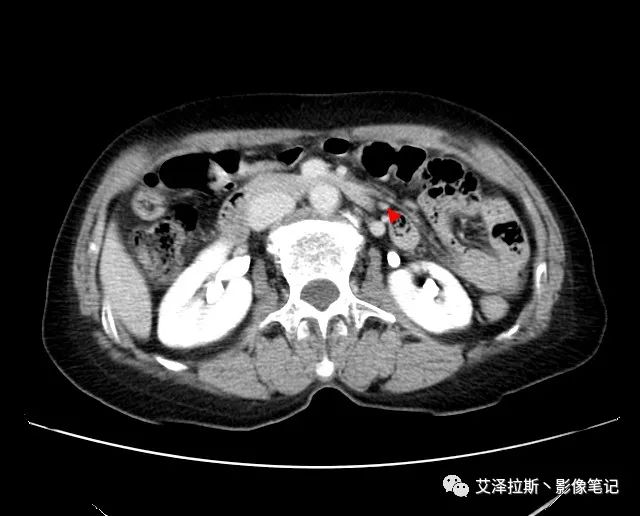

圖1 平掃+增強各期

【影像所見】 胃竇部狹窄,胃壁環形增厚,小彎側見一巨大潰瘍,周圍伴“環堤征”,漿膜面不完整,胃周脂肪見網格狀條索影,病灶與肝臟左葉、胰腺鉤突脂肪間隙消失,增強掃描病灶明顯強化。引流區內約15個區域淋巴結受累。

【診斷意見】 胃竇部胃癌(T4N3期) 該病例腫塊突破漿膜層,與肝臟左葉、胰腺鉤突分界不清,脂肪界面消失,定為T4期; 受累及的淋巴結為15個區域,定為N3; 有無遠處轉移尚不明確,所以M期暫時無法確定。